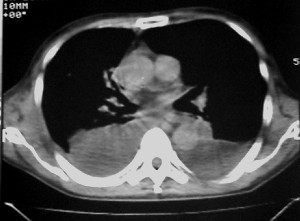

m ,60岁,右上肺ca术后一月。

右侧肺癌术后:肝内可见多个大小不等的低密度结节影。腹腔及双侧胸腔大量积液。考虑:肺癌并胸膜及肝脏转移。

纵隔淋巴结增大,双侧胸水。考虑术后残留,而非复发。

腹水,肝及右肾多发低密度影。考虑转移。

右肾及肝内多发转移瘤,胸水。

肺癌术后 。双侧胸水 纵隔 胸膜 肝脏转移